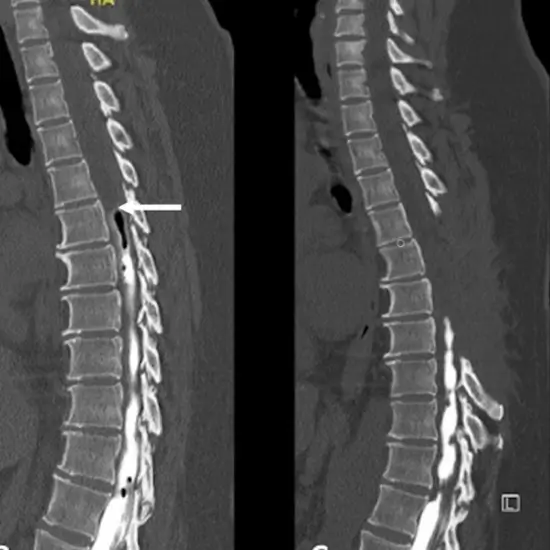

CT Myelogram is an imaging procedure that is used to detect/diagnose the problem in the spinal canal.  It obtains real-time images of the spinal cord, spinal nerve roots, the spinal meninges and other tissues. It helps doctors in detecting abnormalities. It is also known as CT Myelography.